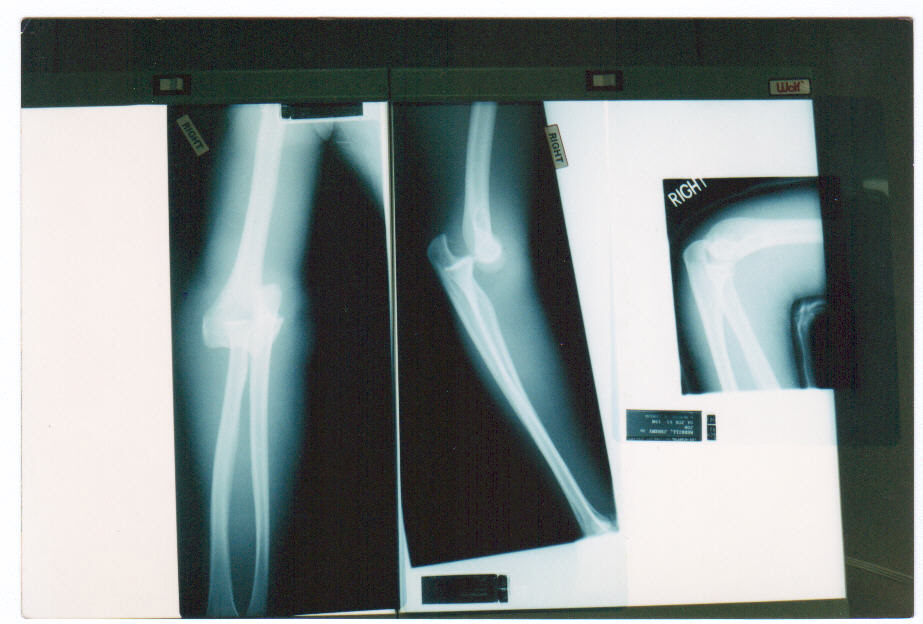

This happend a long time ago. In may of 94 or 95 I was trying to hit 60 mph. I had hit 59 but couldnt break the 60 barrier so I got road tires and a bigger front chain ring. I was young and dumb and tried it at night with no lights. A truck made a left in front of me this is the aftermath. It took a year and seven surgeries (two bone graphs) to get me back on my feet. Obviously this is no fault of the carbon, but 15 yrs later I still have visible shards in my leg to remember my first mountain bike. Now 15 yrs later I am still a bicycle messenger, and I love it.